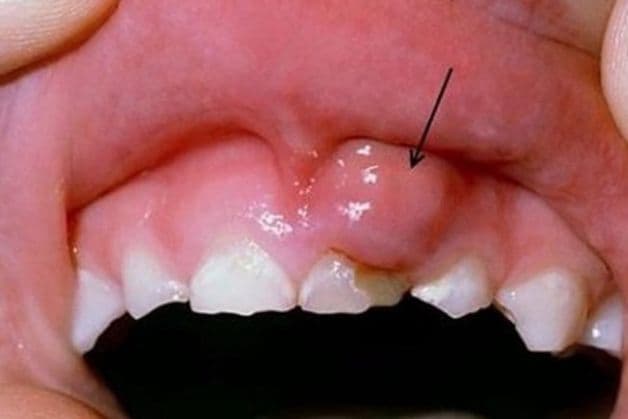

Hình ảnh minh họa chân răng bị sưng mủ.

Sưng mủ là biểu hiện tiêu biểu của việc bị nhiễm trùng tại chỗ. Chân răng bị sưng mủ là triệu chứng cho thấy phần chân răng đã bị nhiễm trùng, hình thành nên mủ. Đây là một dấu hiệu của bệnh viêm chân răng có mủ. Bệnh cảnh báo sức khỏe răng miệng của bạn đang gặp phải các vấn đề nghiêm trọng. Bài viết dưới đây sẽ cho bạn biết thêm những thông tin cơ bản về căn bệnh này: nguyên nhân, dấu hiệu cũng như cách điều trị bệnh.

Như vậy, viêm chân răng là khi tủy răng hoặc vùng lợi (nướu) của người bị viêm nhiễm, tạo nên ổ áp xe. Nếu áp xe nhẹ, có thể dùng thuốc điều trị và nhanh chóng khỏi bệnh nhưng nếu chủ quan, để ổ áp xe lâu dài và tiến triển nặng thì có thể gây ra những bệnh lý khác ảnh hưởng sức khỏe toàn thân.